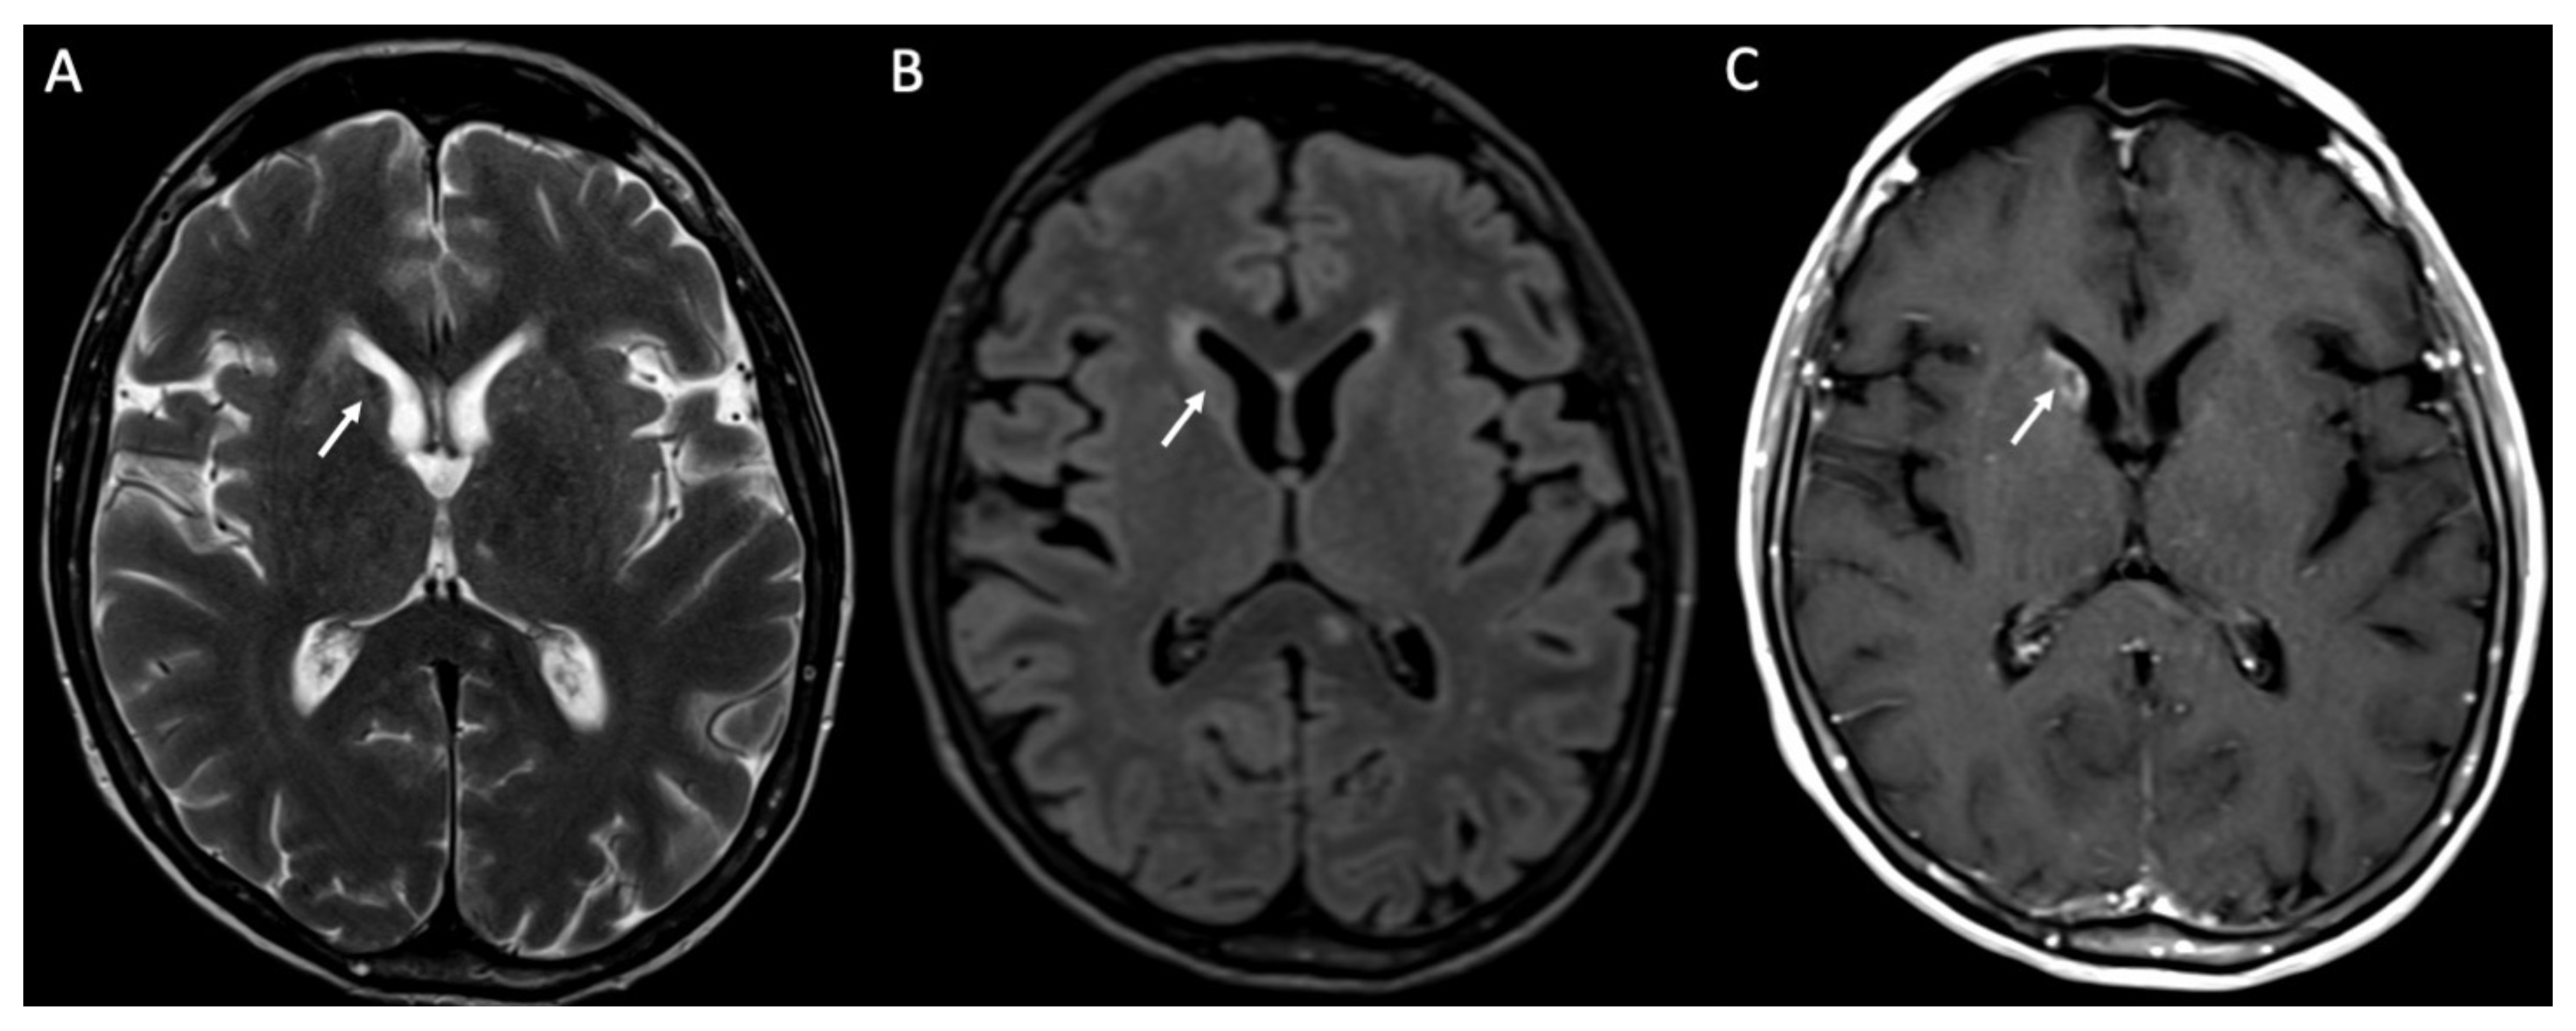

| Piogenic Meningitis | • Cerebrospinal fluid hyperintensity in T1 and FLAIR • Restricted diffusion of the subarachnoid spaces • Meningeal enhancement on T1 and FLAIR |

2. Piogenic Meningitis